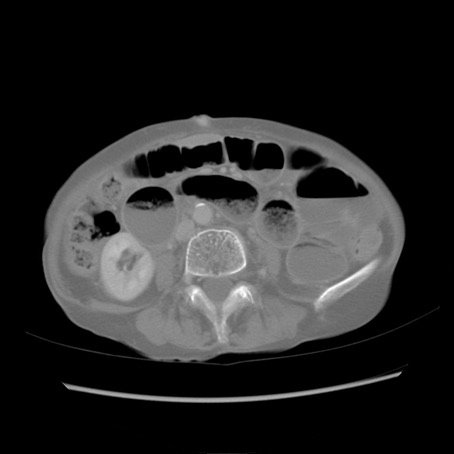

症例25(横断像)

【症例】80歳代女性

【主訴】胸のつかえ感

【現病歴】約9時間前に食後から胸のつかえた感じあり、嘔吐あり、来院。

【既往歴】胃癌(全摘)、胆摘、虫垂炎

【身体所見】心窩部に圧痛あり、反跳痛なし。

【データ】WBC 5700、CRP 0.05